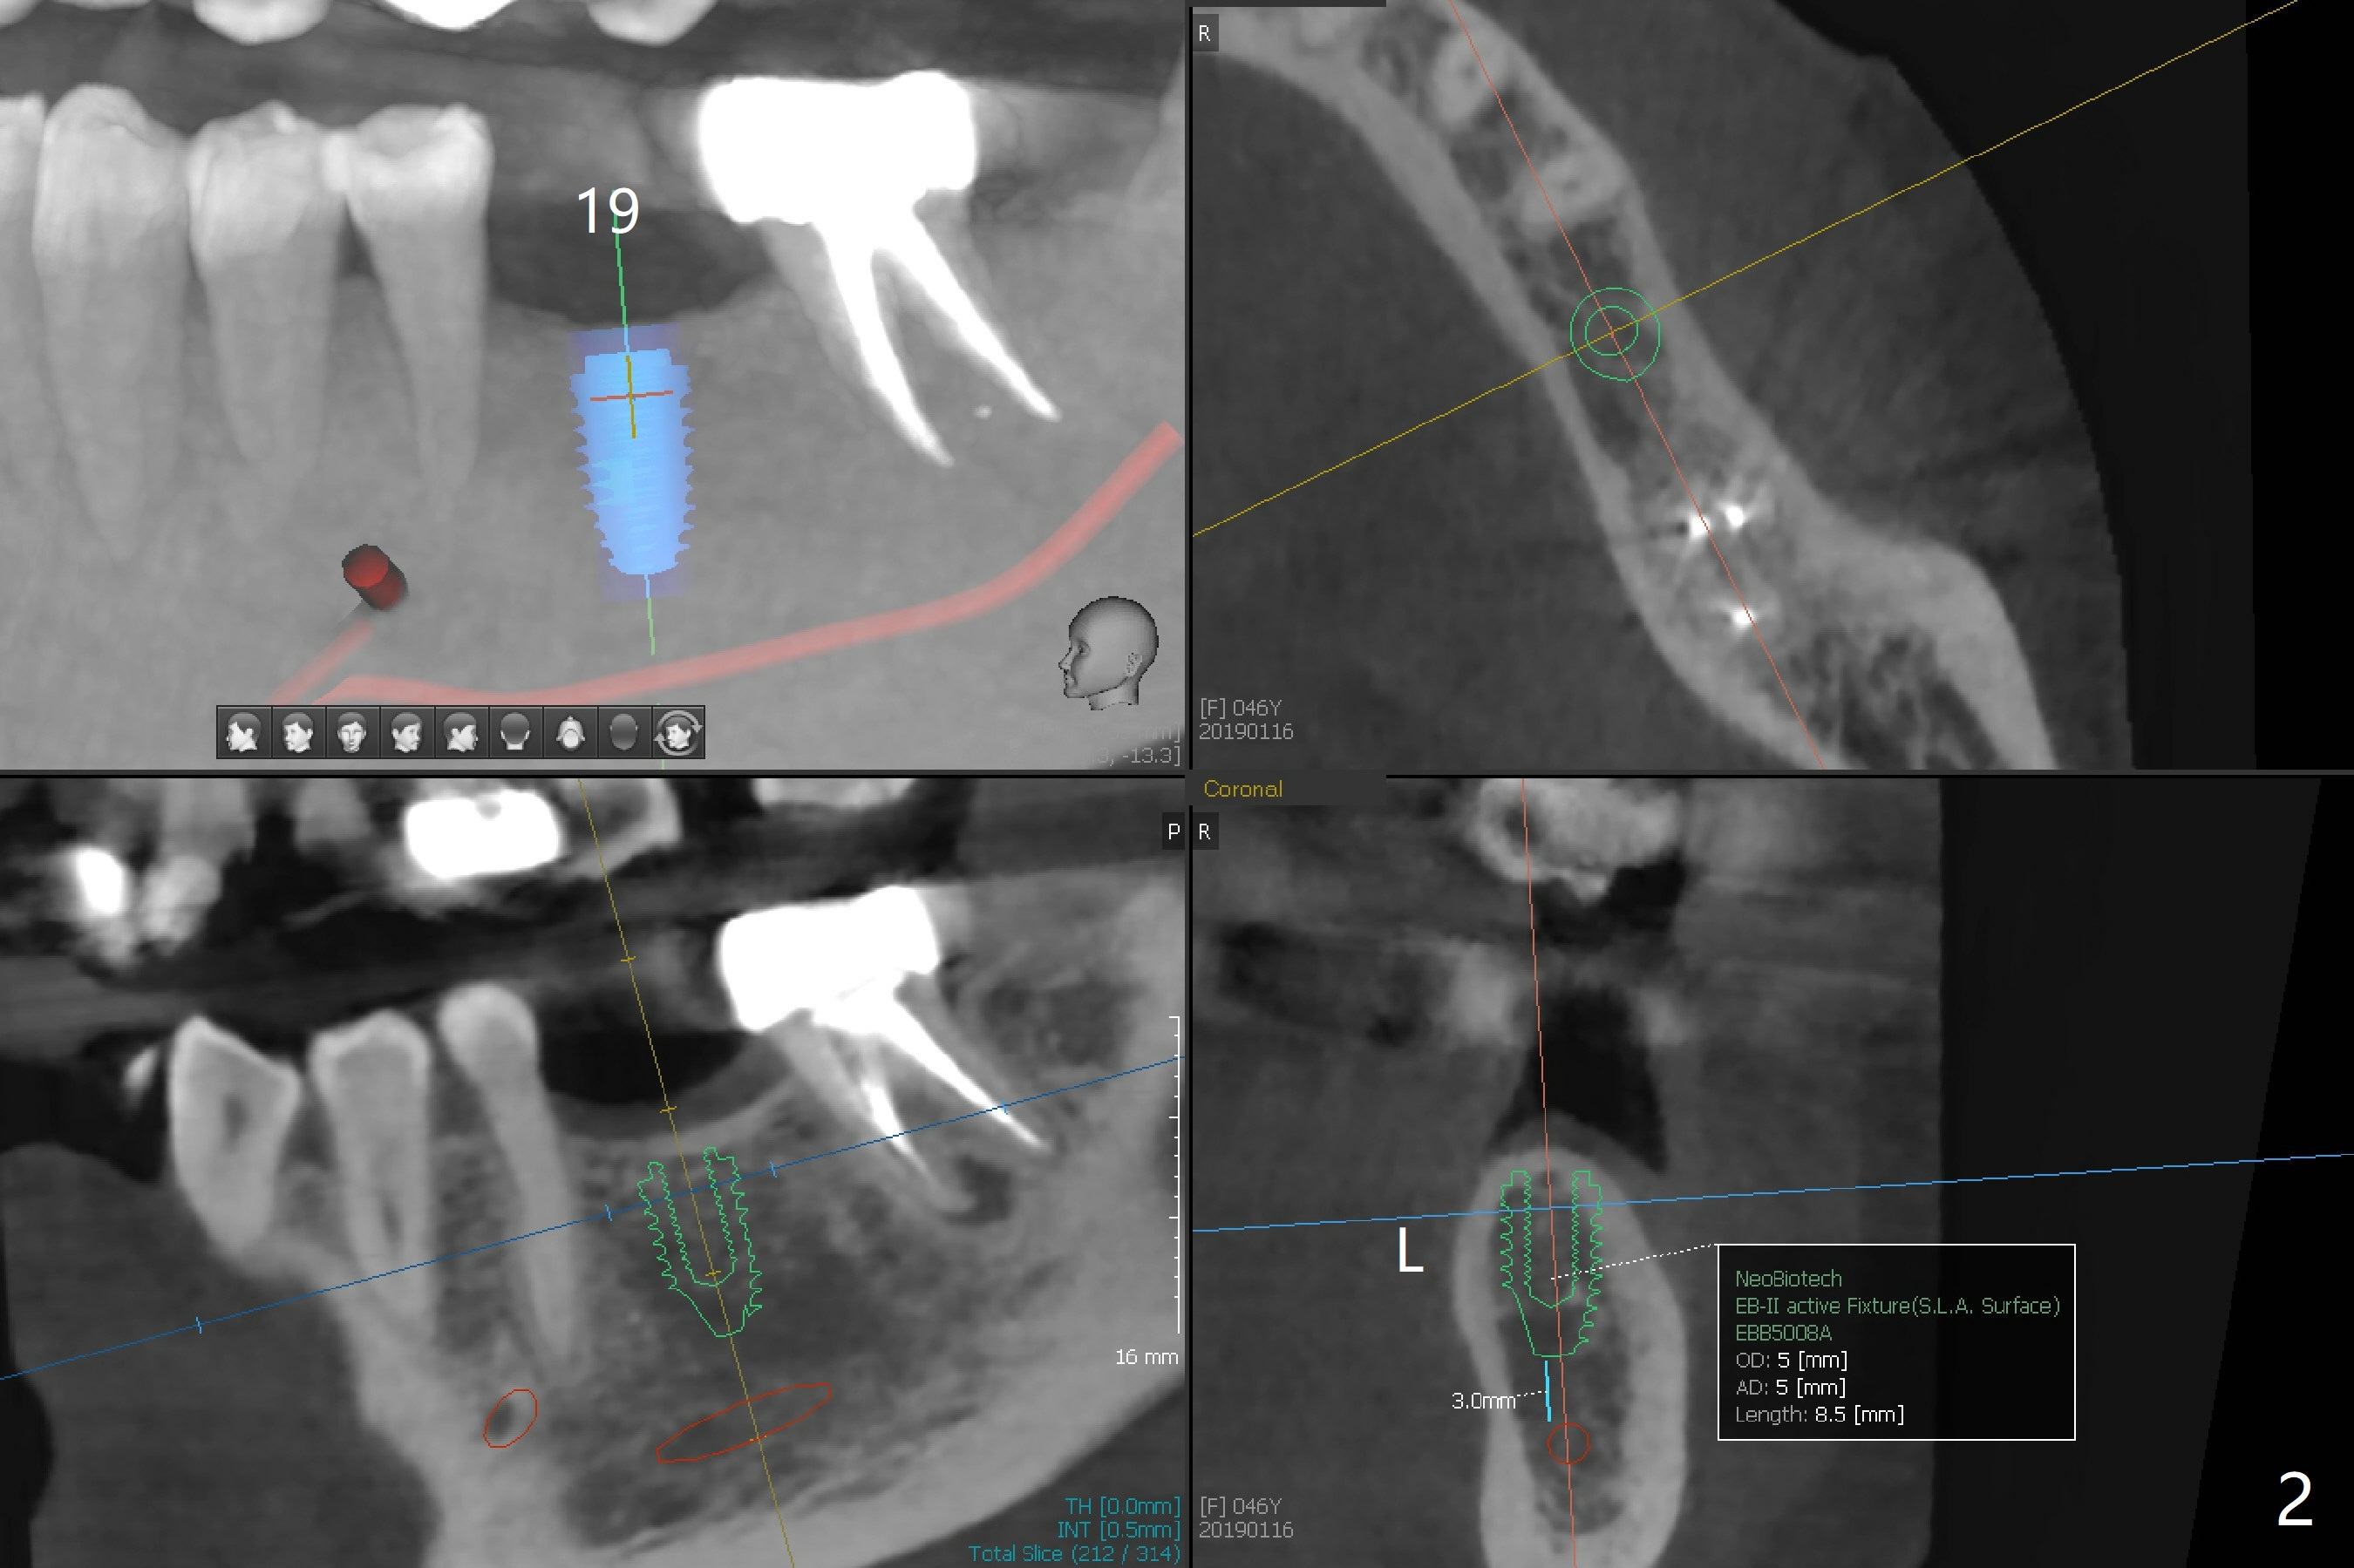

A 46-year-old woman returns for #19 guide 8 and 3 months post cementation at #3 and 30, respectively (Fig.1). A 5x8.5 mm implant appears to be appropriate for the site (Fig.2).